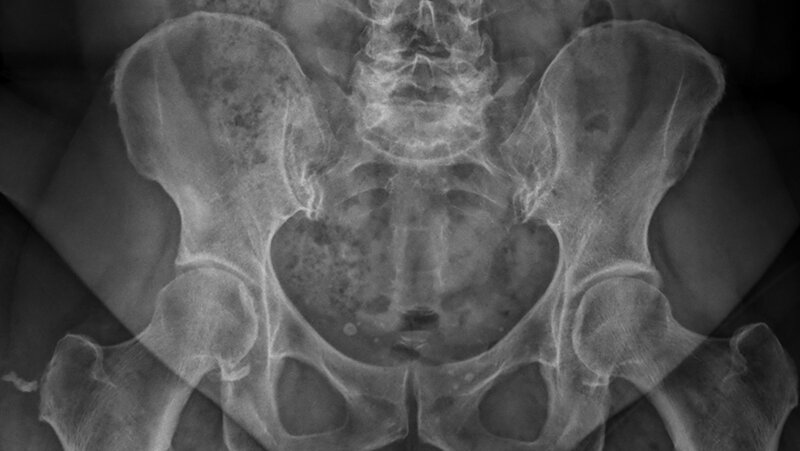

Die Hüftdysplasie verweist auf ein Spektrum von abnormen Veränderungen der Hüftgelenke, die von milden Formen der Instabilität bis zur Gelenkdislokation reichen.

Dysplasia of the hip refers to a spectrum of abnormalities involving the developing hip. These abnormalities range from mild instability to frank dislocation of the joint.